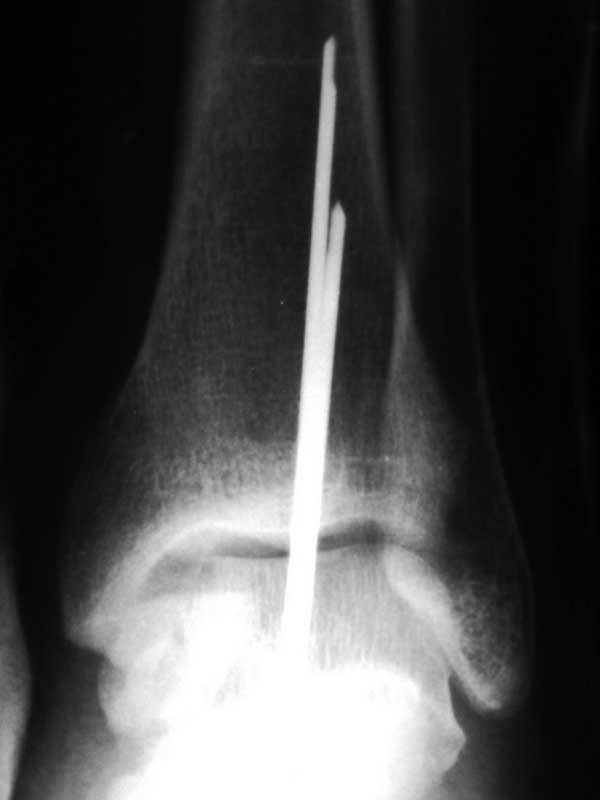

[Ortho] Переломовывих таранной кости

Прямая проекция